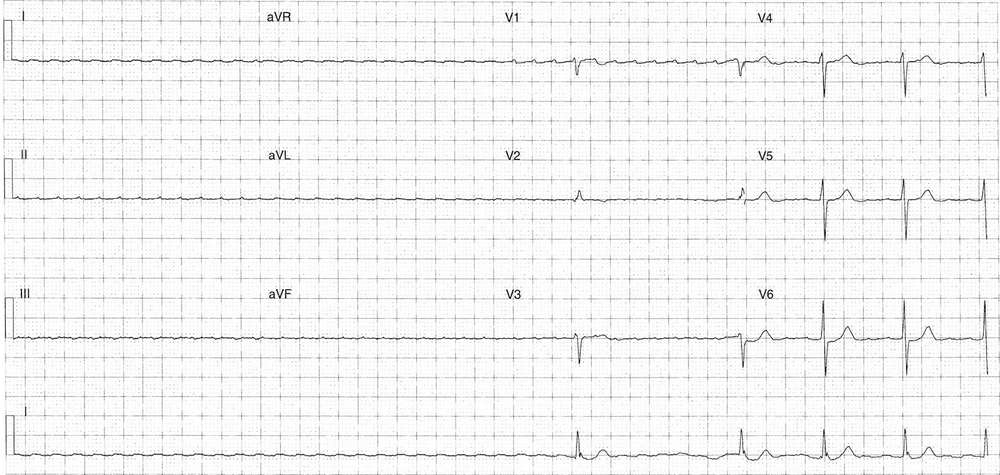

This following ECG was taken during treatment with adenosine, hence the dramatic ventricular pause.

Key features

- Minimum 5.72 sec ventricular pause

- Evidence of atypical flutter waves

- Rate ~290 bpm

- Low voltage

- Positive in lead V1

- Following pause initiation of ventricular activity with increasing rate

- Ventricular 72 bpm (4:1 block) prior to end of ECG tracing

- QRS morphology sames as ECG above